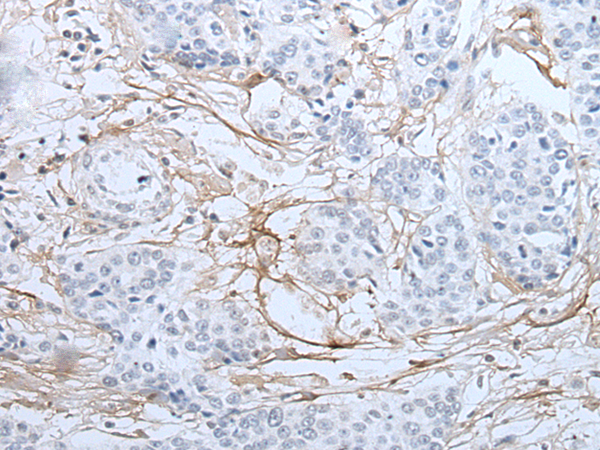

分类: 科研抗体货号: P12761别名: DIRA; IRAP; IL1F3; IL1RA; MVCD4; IL-1RN; IL-1ra; IL-1ra3; ICIL-1RA应用: IHC反应种属: Human